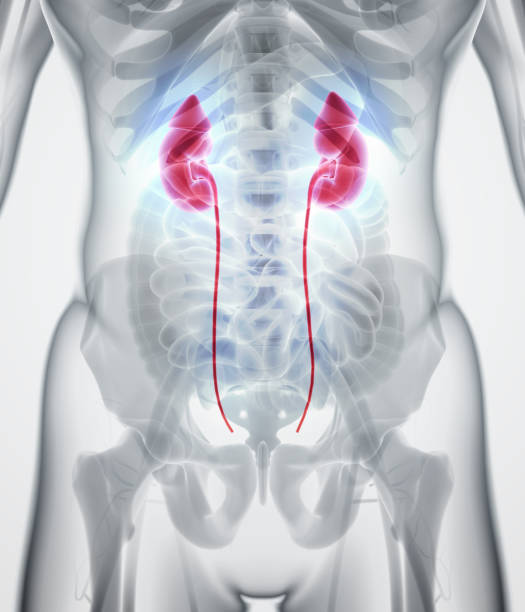

x-ray image of the urinary tract:

Human Urinary System In Gray Xray Stock Photo – Download Image Now …

Side View Of Human Urinary System In Gray X-ray Stock Photos – Image …

Female Urinary System Royalty Free Stock Photo – Image: 36221015